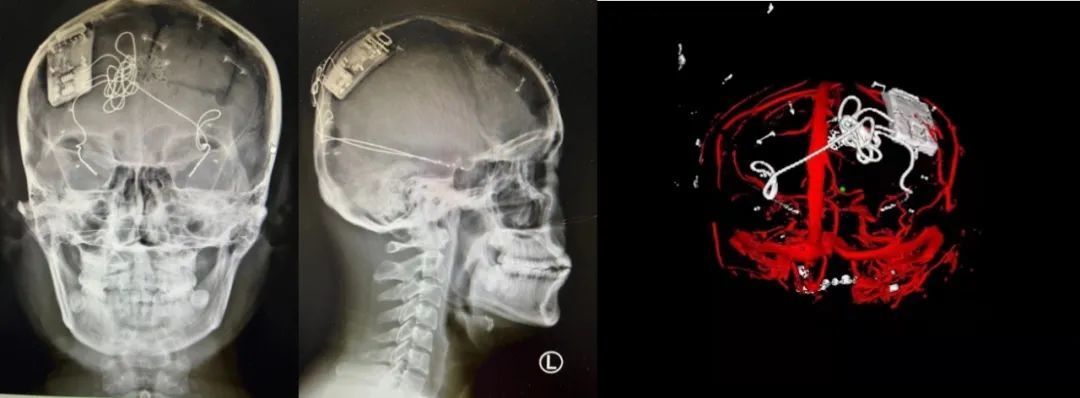

本次手術(shù)過程順利,術(shù)中刺激器各項指標(biāo)均工作正常,術(shù)后重建顯示電極位置精準(zhǔn),腦電信號清晰。患者為男性,入院后診斷為雙側(cè)顳葉癲癇,此類癲癇為開顱手術(shù)的相對禁忌癥,在藥物無法控制的情況下,傳統(tǒng)治療效果欠佳 。

術(shù)前經(jīng)過宣武醫(yī)院癲癇多學(xué)科專家團(tuán)隊詳細(xì)的臨床評估,包括視頻腦電監(jiān)測、頭顱磁共振及三維 CT 掃描、腦核醫(yī)學(xué)檢查等,全面評估了患者病情及致癇灶定位情況。

由于患者臨床診斷為雙側(cè)顳葉癲癇伴海馬硬化,無法通過致癇灶切除等傳統(tǒng)外科手術(shù)方式獲益,決定進(jìn)行閉環(huán)反應(yīng)性神經(jīng)刺激系統(tǒng)植入手術(shù)治療。并根據(jù)閉環(huán)神經(jīng)刺激技術(shù)特點,為患者“量身定制”植入方案,尤其是電極植入位點和脈沖發(fā)生器固定部位等,為手術(shù)的順利實施奠定了良好基礎(chǔ)。

團(tuán)隊根據(jù)術(shù)前計劃,在手術(shù)機(jī)器人輔助下完成雙海馬長軸電極及 IPG 植入,術(shù)后重建顯示電極位置精準(zhǔn),腦電信號清晰。術(shù)后第二天,患者即下床活動,身體狀況恢復(fù)良好。